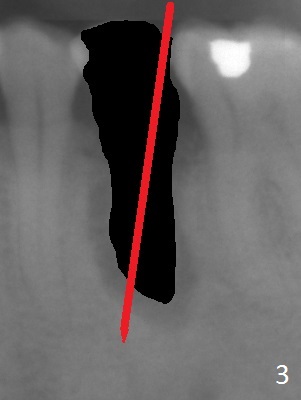

A 53-year-old man (probably bruxer, long roots) has 3 missing teeth (Fig.1 #14,18,29) and 1 fractured tooth (Fig.2 #20). The fractue is associated with deep buccal pockets. The buccal plate is most likely defective. After extraction (Metronidazole), start osteotomy lingual and mesial (Fig.3 red long arrow) to reduce damage to the Mental Loop (Fig.4 red dashed line). Damage to the Incisive Canal (yellow dashed line, the continuum of the Inferior Alveolar Canal after giving off the Mental Loop) is less significant. Since the defect is long, use the longest implant and place it deep. A long abutment (7 mm, green) with 5 mm cuff (pink) is required. To have sufficient buccal gap for bone graft and probably membrane, the smallest two-piece implant is necessary (3.8 mm).